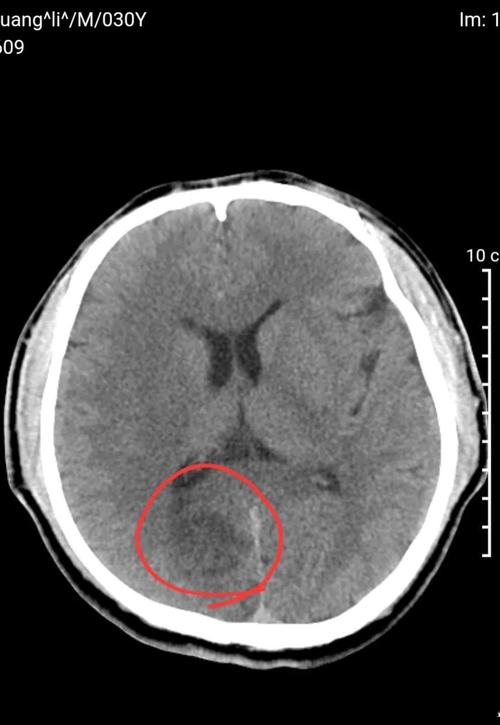

- 后颅窝(脑干、小脑)梗塞: 由于骨质伪影干扰,CT对后颅窝梗塞的显示效果远不如MRI。